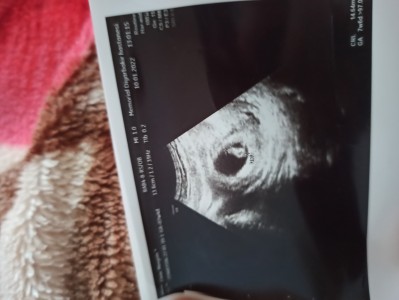

1. image

Bu şekile olan bebeği ne oldu ...

Kaç haftalık canım küçük.gibi daha

8+2 hafat

Kesesi yuvarlak kız diyim.